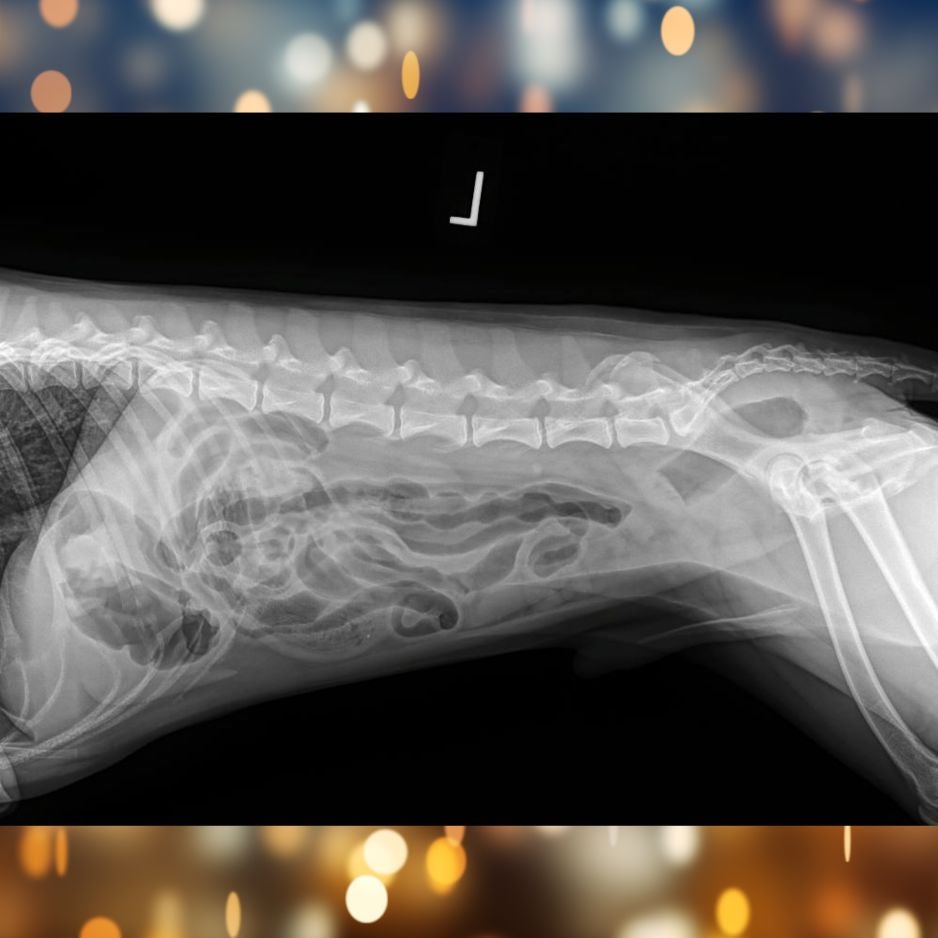

Tito X-rays Day 2

Unfortunately, the material did not move on its own, which meant Tito needed surgery to safely remove the obstruction.